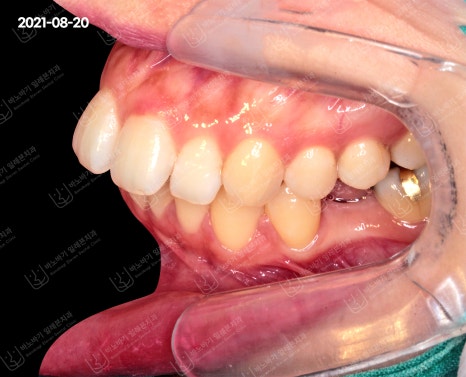

측면 교합도 살펴보았습니다. 앞니가 앞으로 크게 기울어져 입을 도드라져 보이게 만드는 핵심적인 원인으로 작용했네요.

게다가 어금니(제2소구치) 또한 탈락한 것으로 확인되었습니다. 돌출입 교정 시에 이런 부분을 종합하여 계획을 수립했습니다.